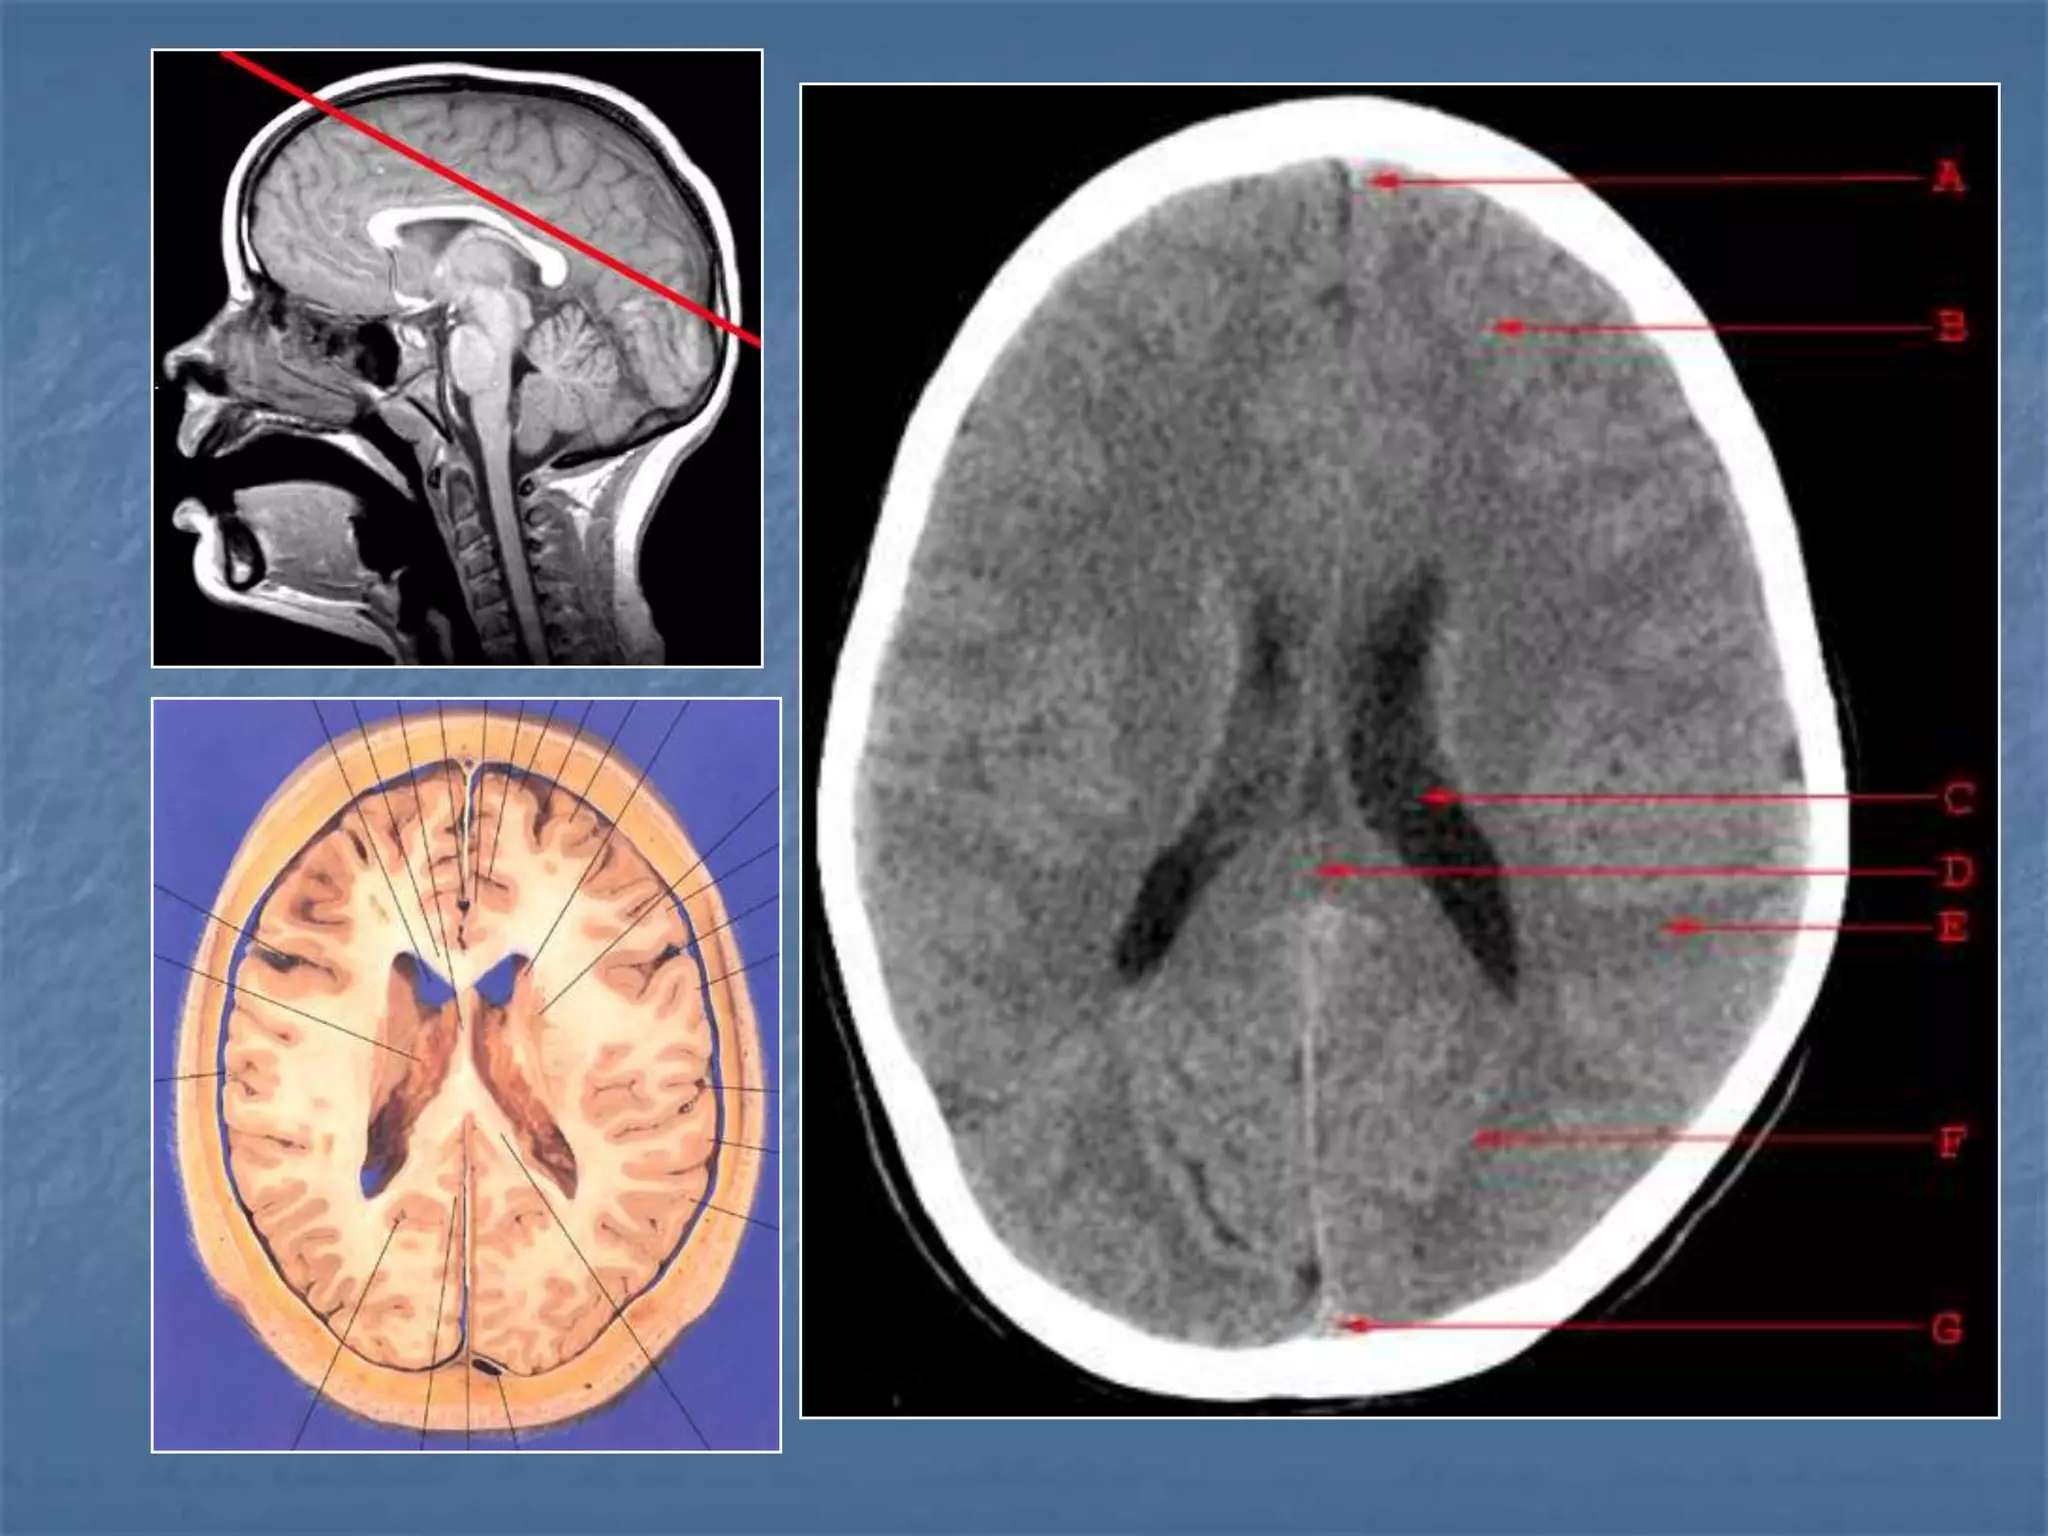

How the CT study is usually planned…

15-20 degree

angulation to

canthomeatal line

to decrease

radiation to the

lens.

Brain Window Bone Window

Descriptive Terms …….

 Hypodense / Hypointense

 Isodense / Isointense

 Hyperdense / Hyperintense

Hounsfield Units

AIR - - 1000

FAT - - 30 to -100

CSF - 0

GREY MATTER - 32 - 41

WHITE MATTER - 23 - 34

ACUTE BLOOD - 56 - 76

CALCIFICATION - 60 - 400

BONE - 1000